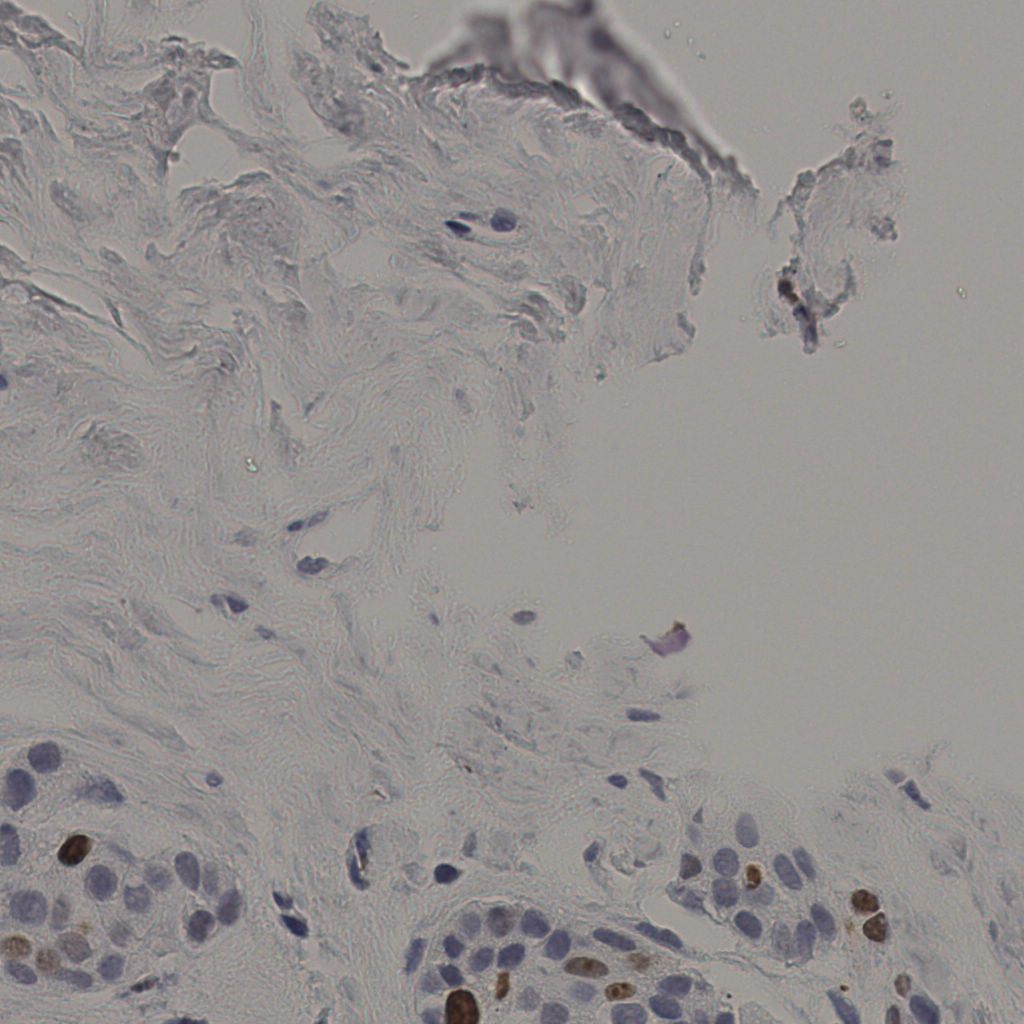

缩略图

标记后

标记前